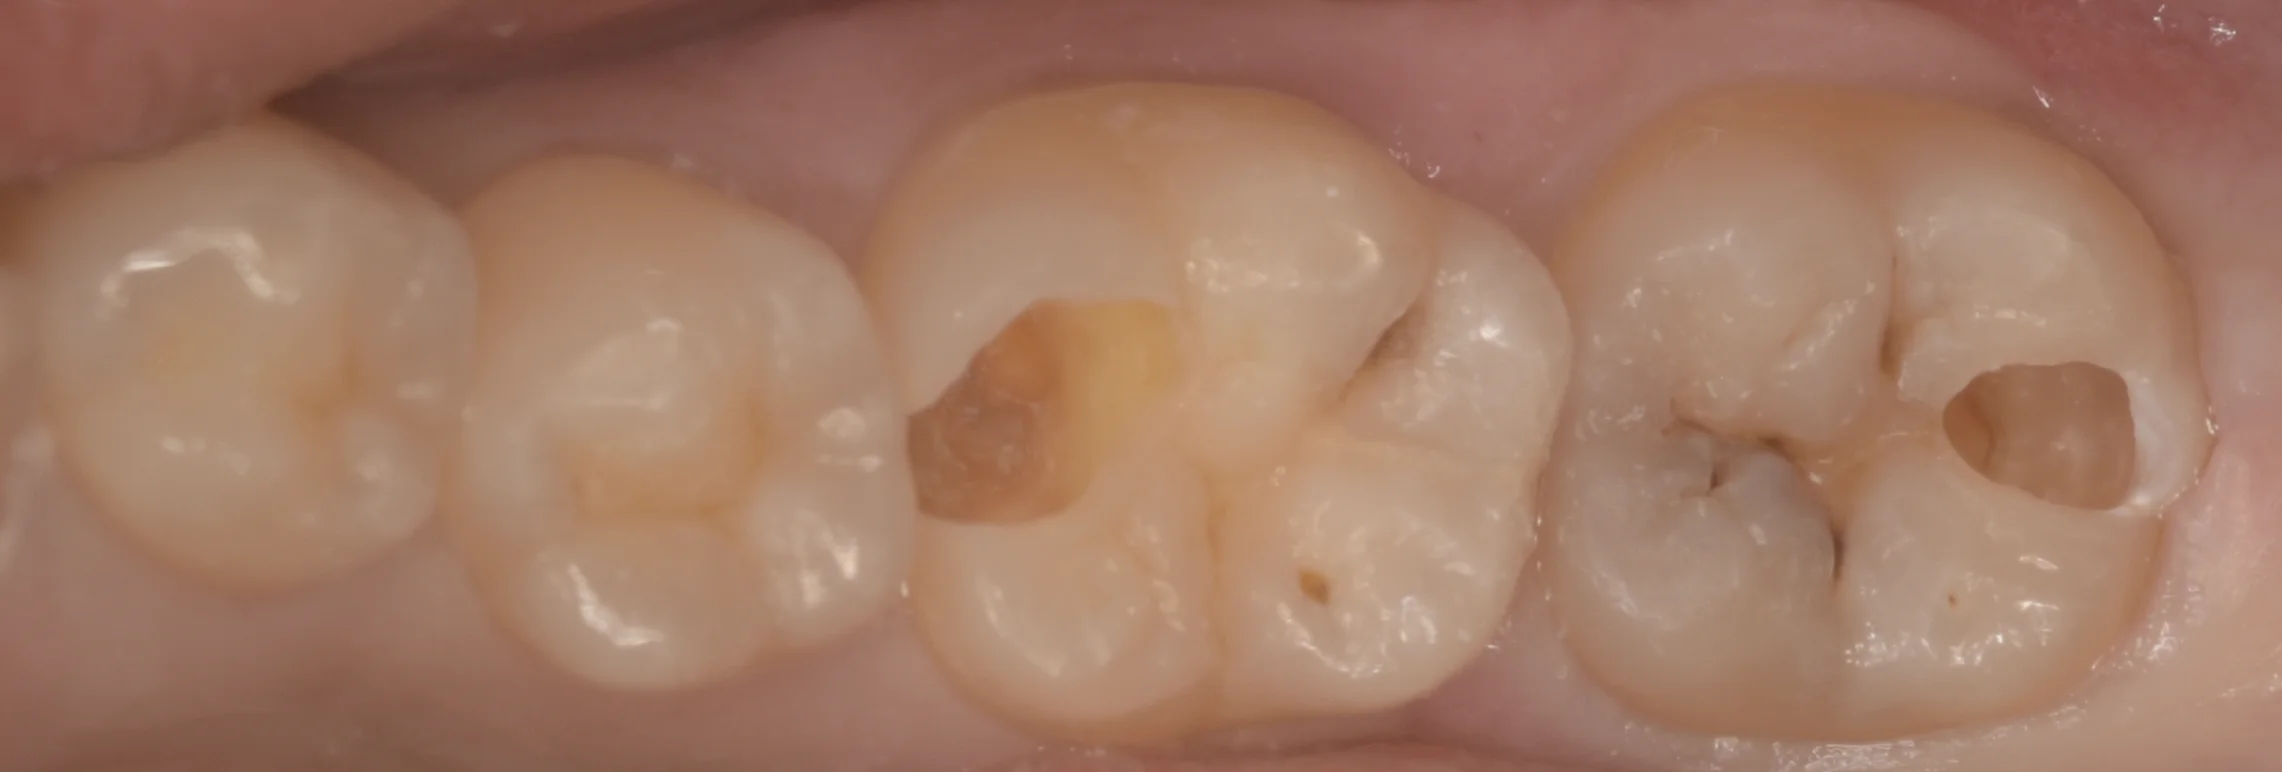

虫歯を見やすくするために軽く削ったのがこちらになります。

どちらも内部で非常に大きく深くなっていました。

取り切ったのがこちらになります。

見た目上はあまり大きくないように思えますが、実は内部で非常に大きく進んでおり、どちらも神経がうっすら見えてるレベルでした。

右側の歯の溝の部分で黒いのが残っており、手をつけていない場所がありますが、この場所はレントゲン診査にて内部で大きく進行している様子が見られなかったため、フッ化物による管理で対応できると判断したため今回は介入しませんでした。